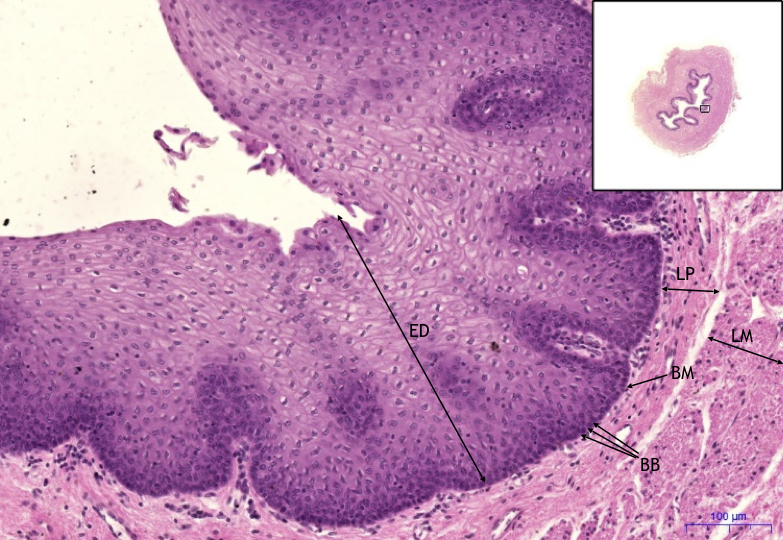

Jícen/Esophagus, HE 11,2x

- ED – dlaždicový epitel/squamous epithelium

- BM – bazální membrána/ basement membrane

- BB – bazální vrstva buněk / basal layer of cells

- LP – lamina propria

- LM – lamina muscularis